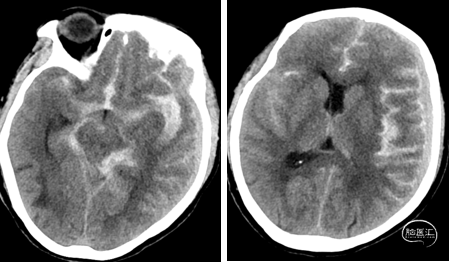

头颅CT

术前

术后第一天